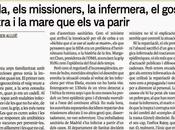

Reconstrucción tridimensional de una célula dendrítica madura (en gris) donde el VIH (en rojo) se almacena con el nuevo receptor identificado, Siglec-1 (en verde). Imagen: IrsiCaixa